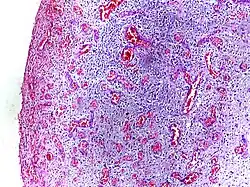

Morphologic patterns

Specific patterns of acute and chronic inflammation are seen during particular situations that arise in the body, such as when inflammation occurs on an epithelial surface, or pyogenic bacteria are involved.

- Fibrinous inflammation: Inflammation resulting in a large increase in vascular permeability allows fibrin to pass through the blood vessels. If an appropriate procoagulative stimulus is present, such as cancer cells,[9] a fibrinous exudate is deposited. This is commonly seen in serous cavities, where the conversion of fibrinous exudate into a scar can occur between serous membranes, limiting their function. The deposit sometimes forms a pseudomembrane sheet. During inflammation of the intestine (pseudomembranous colitis), pseudomembranous tubes can be formed.